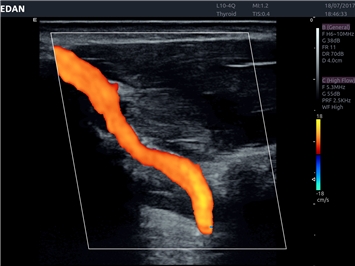

Система Acclarix LX4 оптимально подходит для:

• Сосудистой диагностики

Трехмерная реконструкция ЦДК:

Да

Направленный энергетический допплер:

Энергетический допплер:

Цветовой допплер:

• Автоматическое измерение толщины интима-медиа